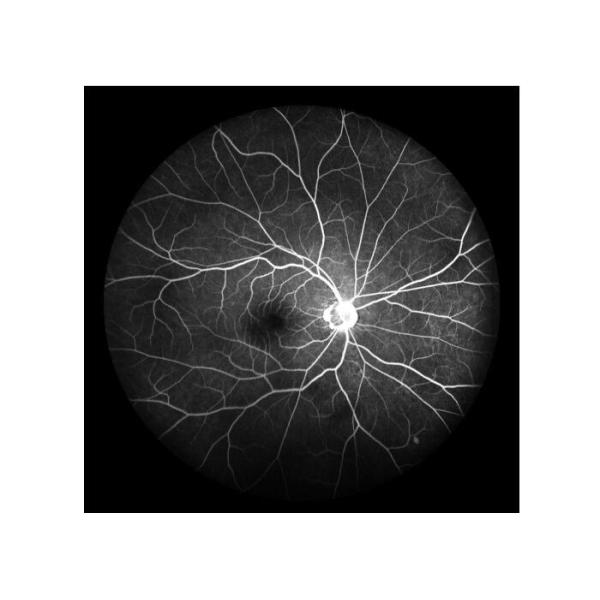

| 1 |  | Fundus Fluorescein Angiography(FFA): Retinal circulatory change | 1) ”Golden standard” to judge retina disease 2) To reflect the physiological pathology of retinal blood vessels to capillaries 3) To comprehensively inspect diseases undetected in normal fundus examination |

Cases

Retina Angiograph Digital 160° Ophthalmic Equipment Images |